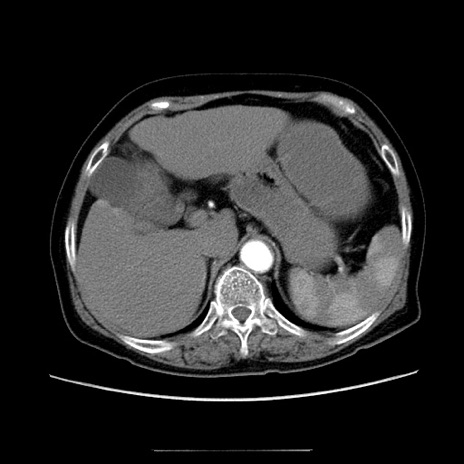

症例5(横断像)

【症例】70歳代女性

【主訴】お腹が張る

【現病歴】1週間くらい前から腹部膨満の自覚あり。昨日夜から増悪したため、本日救急外来受診。

【身体所見】意識清明、BT 36.5℃、BP 165/106mmHg、HR 80bpm、SpO2 98%、腹部:膨満、軟、自発痛・圧痛なし、触診にて不快感あり、腸蠕動音:減弱

【データ】WBC 12600、CRP 1.04